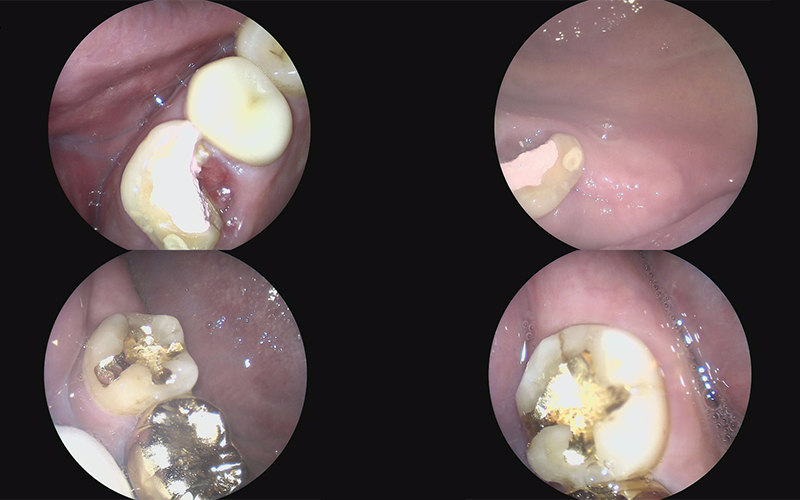

구강 카메라도 촬영하여

구강 내 상황을 꼼꼼하게 체크하였고

환자분께도 보여드리며 설명드렸습니다.